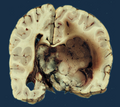

Gross

Features: [1]

- Adhere to ventricular walls.

- Circumscribed.

- Villous architecture.

- 50% lateral ventricles.

- 5% third ventricle.

- 40% fourth ventricle.

- 5% multiple tumours or cerebellopontine angle.